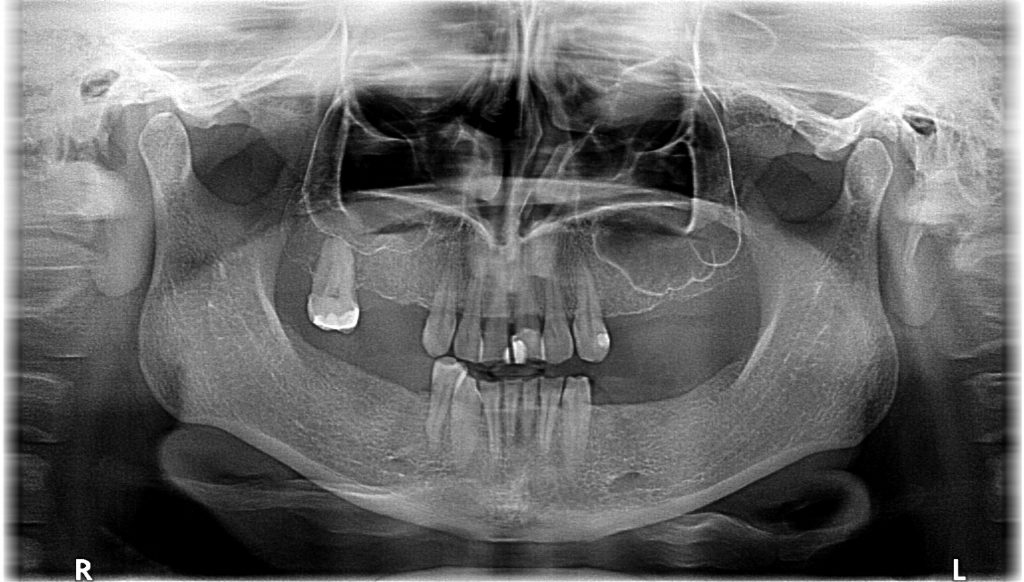

Streszczenie: W artykule opisano przypadek leczenia ortodontyczno-implantoprotetycznego pacjentki z brakami skrzydłowymi i międzyzębowym szczęki i żuchwy. Plan leczenia obejmował: przygotowanie ortodontyczne, podniesienie dna obu zatok szczękowych (sinus lift), implantacje oraz wykonanie prac protetycznych. Po zakończeniu leczenia osiągnięto zadowalający sukces leczniczy, funkcjonalny oraz estetyczny.

Summary: The article describes a case of orthodontic and implantoprosthetic treatment of a patient with free-end and interdental saddle of the maxilla and mandible. The treatment plan included orthodontic preparation, lifting the bottom of both maxillary sinuses (sinus lift), implantation and the fabrication of restorations. After the treatment, satisfactory therapeutic, functional and aesthetic success was achieved.